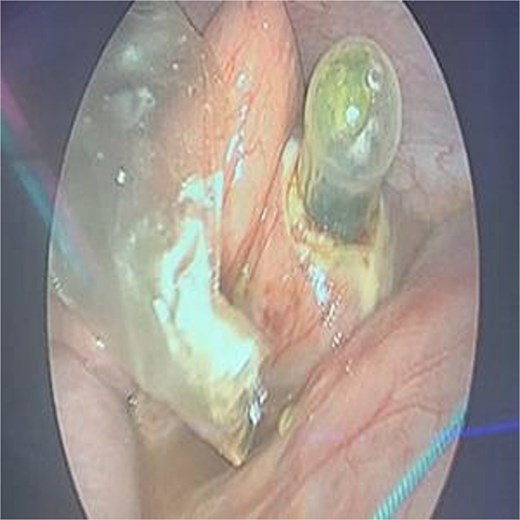

The patient was stabilized with IV fluids, nasogastric decompression, and antibiotics. Emergency laparoscopic surgery was performed using a trans-umbilical Hasson technique for camera access and two 5 mm working ports. Intraoperative findings included a foreign body lodged in the proximal jejunum without adhesions. Transparietal suspension sutures were used to facilitate exposure. Enterotomy was performed, and the object was extracted via an endo-bag. The enterotomy site was closed using STRATAFIX™ 3.0 suture (Figs 2 and 3). A laparoscopic appendectomy was concurrently performed via the umbilical incision using the in-out technique (Fig. 4).